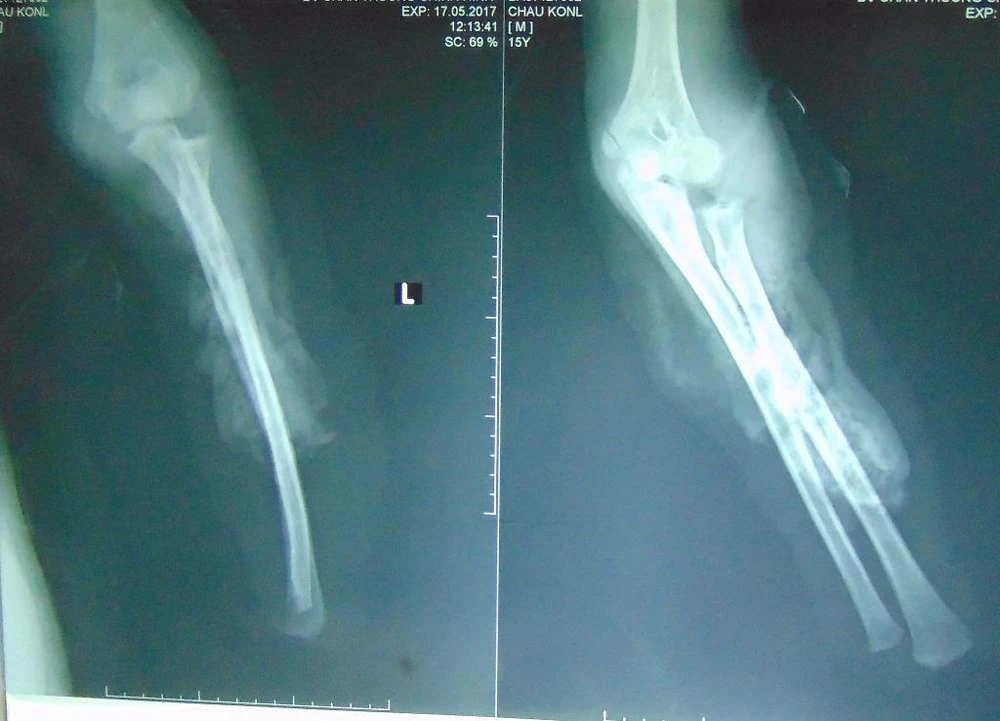

Kết quả chụp X-quang cho thấy cánh tay trái bệnh nhân bị đứt lìa và dập nát.

Kết quả chụp X-quang cho thấy cánh tay trái của bệnh nhân bị đứt lìa và dập nát. Ảnh: TRẦN NGỌC